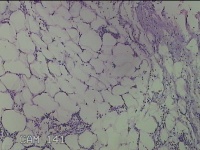

性别

男

年龄

56岁

临床诊断

右侧腋下结节

一般病史

标本名称

大体所见

灰白粉红色组织2.3x2x0.8cm一块,表面带梭形皮肤2.3x2cm,皮下见结节2x1cm一个,结节部分已切开,见结节呈囊性,囊内有少许灰白色角化物,囊壁厚0.1cm。

炎性病变。